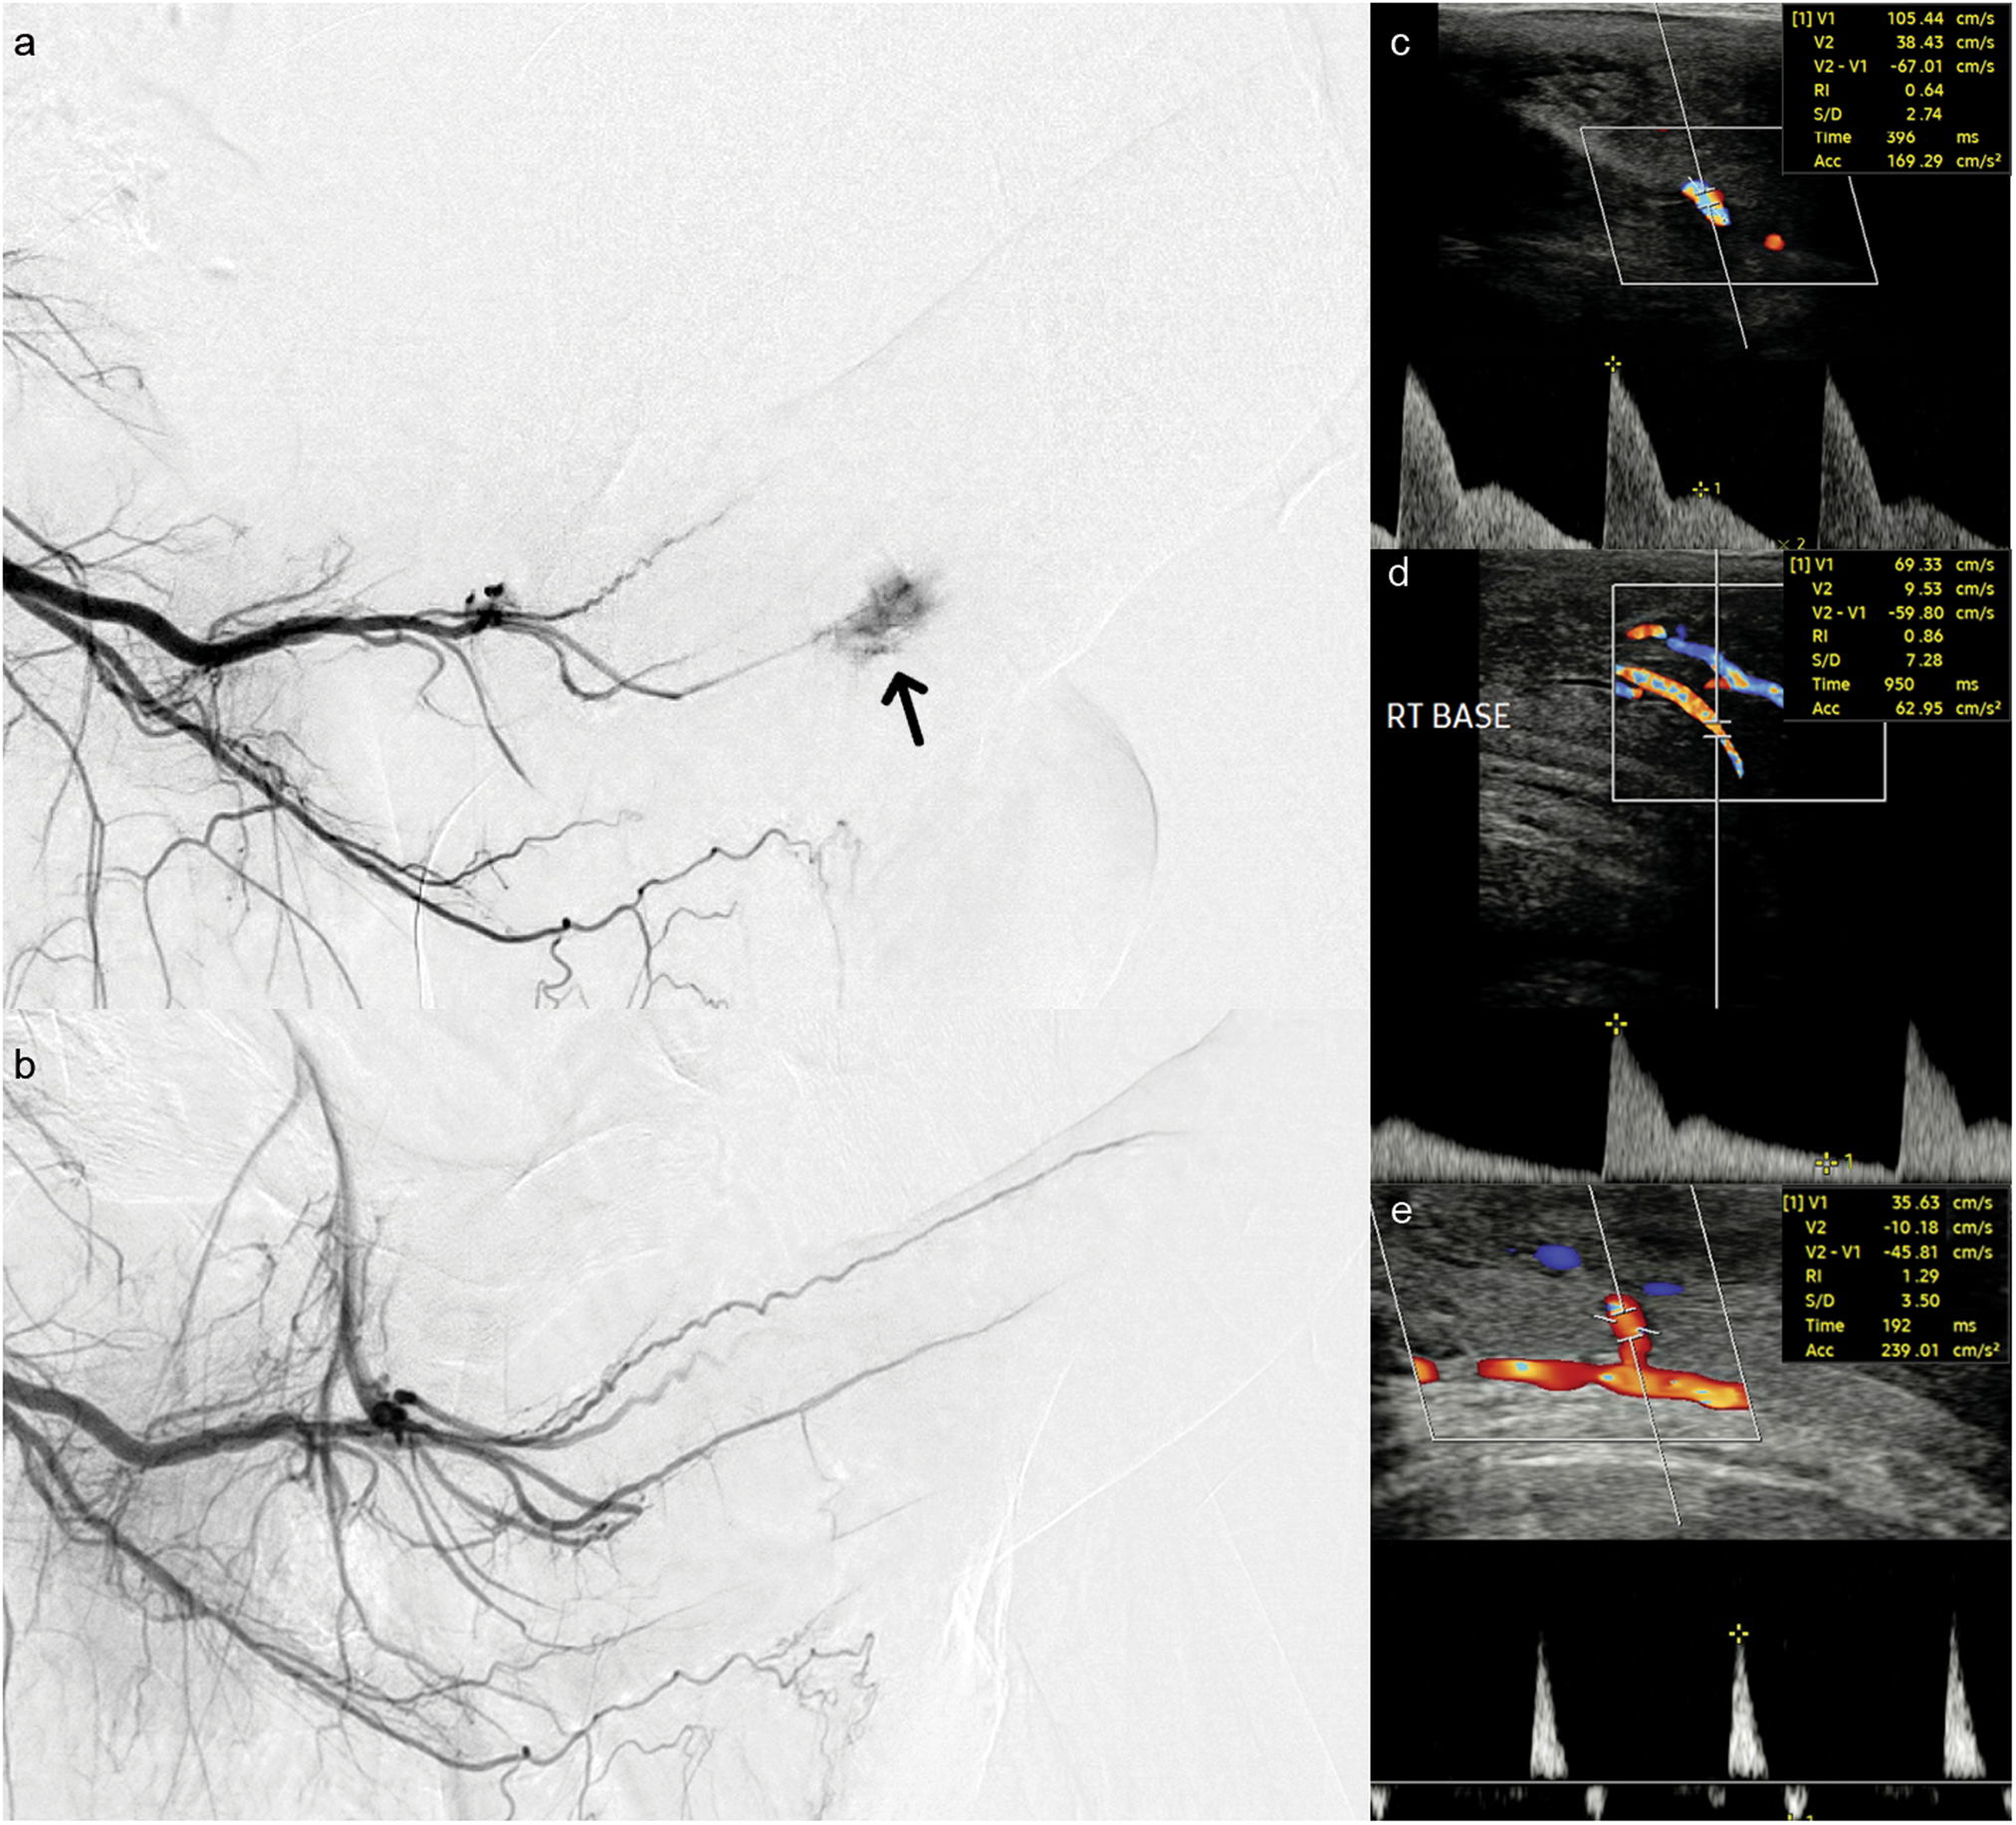

Fig. 1: Selected angiographic and ultrasound images from a case of non-ischemic priapism.

a Angiogram from the distal internal pudendal artery showing AVF (black arrow) arising from a the right cavernosal artery. b Post embolization angiogram showing resolution of the AVF and normal filling of the penile artery and branches. c Initial diagnostic CDUS trace showing a classical high flow low resistance waveform of NiP (PSV 105 cm/s, EDV 38 cm/s, RI 0.64). d Follow up CDUS at 1 week. The patient had a flaccid penis. The waveform is abnormal with the persistent forward flow in diastole (but much improved compared to the initial diagnostic scan (PSV 69 cm/s, EDV 9.5 cm/s, RI 0.86). e Subsequent CDUS at 3 months a low flow, high resistance waveform (PSV 39 cm/s, EDV -10 cm/s, RI 1.29). AVF arteriovenous fistula, NiP non-ischemic priapism, CDUS colour doppler ultrasound, PSV peak systolic velocity, EDV end diastolic velocity, RI resistive index.